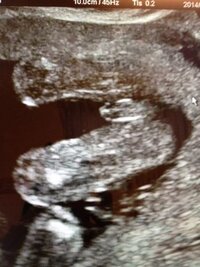

Jul 01, · 安定期に入ると、気になってくるのが赤ちゃんの性別ですよね。男の子、女の子、どちらの性別なのか、ママやパパはワクワクドキドキしていることでしょう。一般的に、赤ちゃんの性別はいつごろ判明するのでしょうか。エコー(超音波)検査で確実にわかるものなのでしょうか。Jun 30, · エコーによる診断で判明しやすい 赤ちゃんの性別は、定期的な妊婦健診のエコーで判明するのが一般的です。医師が外性器(陰茎)のあるなしで判断することがほとんどです。赤ちゃんの向きによっては、なかなか判明しないこともあります。Oct 22, 18 · 赤ちゃんの性別は、産婦人科の検診で行われるエコー検査(超音波検査)で知ることができます。 医師が性別を判断する決めては、男女それぞれの外性器です。

Nov 07, 19 · 赤ちゃんの性別は、産婦人科でのエコー検査によって性別判定が可能です。 ただし、エコー検査を行っているときに、赤ちゃんが背中やお尻を向けていたり、足を閉じていたり、手など他の体の部分がかぶさっていたりすると、判別できないこともあります。Sep 05, 17 · エコー写真撮影時のエピソード: 初めてパパが一緒に見た赤ちゃんのエコーです。4dエコーが初めてだったので、赤ちゃんがここまで見えた事や、まだまだ小さいのに元気な動きが見えた事に二人で感動しました。 それに、このエコーで性別もわかりました。妊娠。赤ちゃん。性別エコー写真のmixiコミュニティ。妊娠中のママさんへ 先輩ママさんへ 我が子の性別エコー写真(超音波、3D、4D)専門のコミュを作成しましたぁ~ こちらのコミュでは 性別確定された方 まだ性別わからない方